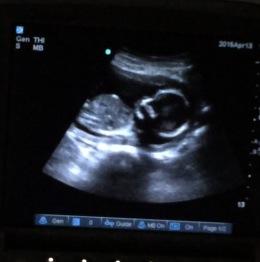

I had posted a few weeks ago that I went for a korean scan off post, it lasted 1:56 and the lady said she didnt she penis. Ok, well I had my 17 wk check up and Dr asked if I wanted to see baby. Of course!! Baby was moving like crazy and she couldn't get an actual potty shot but I have a few shots. So, I took video and these pictures are from the video.

My question, Do you see any gender clues? Skull??? Thank you for looking!!!

Baby looking up, head on right.

Attachment 24767